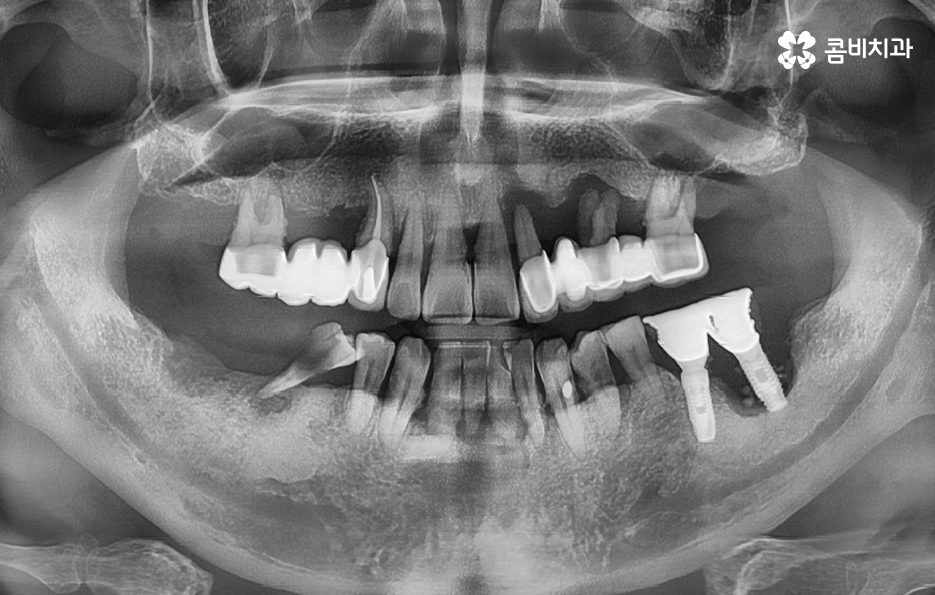

위 환자분의 케이스를 살펴보면 임플란트 시술 후 임플란트 주위염이 발생되어 이미 치조골이 상당히 녹았을 정도로 엑스레이 상에서도 관찰할 수 있어요

임플란트는 보편적으로 분리형이 주로 사용되고 있는데 임플란트의 인공치근은 잇몸 뼈와 골유착이 되어 단단하게 고정이 되어 있고 그 위에 지대주와 보철물이 연결되어 있는 형태이기 때문에 임플란투 수명에 있어서 임플란트의 인공치근 부분이 염증으로 인해 잇몸 뼈가 녹게 되면 임플란트 자체도 흔들리게 되고 결국 제거 후 재수술을 해야 될 수 있어요